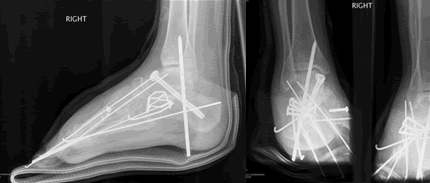

At 28 and already having sixteen surgical procedures behind me, life was not going as I had planned. I had left three jobs in the last year, one which I really loved, all because of the severe foot pain that I lived with everyday. The cause of the pain made a solution especially difficult. I had a congenital neuropathy called, Charcot Marie Tooth Disease, and a bone disease known as, Osteogenesis Imperfecta, along with many serious injuries over the past ten years making mine an especially complicated case. My body felt much older than it's young looks betrayed.

I was referred to Doctor Leavitt at the very beginning of 2008. When I met Dr. Leavitt for the first time I left knowing two things. First, my case would be difficult and even impossible for most surgeons (in fact many doctor's in the past refused to operate on me because of the complicated nature of my case). Second, Dr. Leavitt was the right man. I've never left a consultation feeling both so overwhelmed at what was in store for me in terms of pain, recovery, and rehab and yet so at ease that I was in the most capable hands. To say Dr. Leavitt is thorough would be an understatement. In fact, I had four visits in the month leading up to my surgery and I even received a phone call on a Sunday afternoon from Dr. Leavitt to confirm something he was working on at home. I took comfort knowing that I was going into a situation that had been planned out down to every detail and every contingency was accounted for. Simply put, Doctor Leavitt is the most accessible and capable doctor I have ever met.